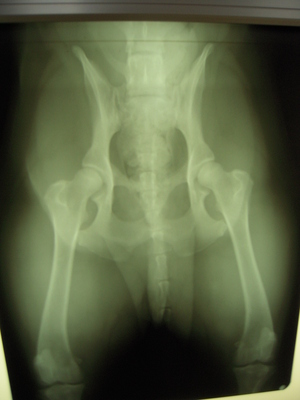

座り方が気になったので

股関節のレントゲンを

とってもらったラビッヂ。

「きれいです」とのことで安心~

これでフリスビーを

思いっきりできるね!